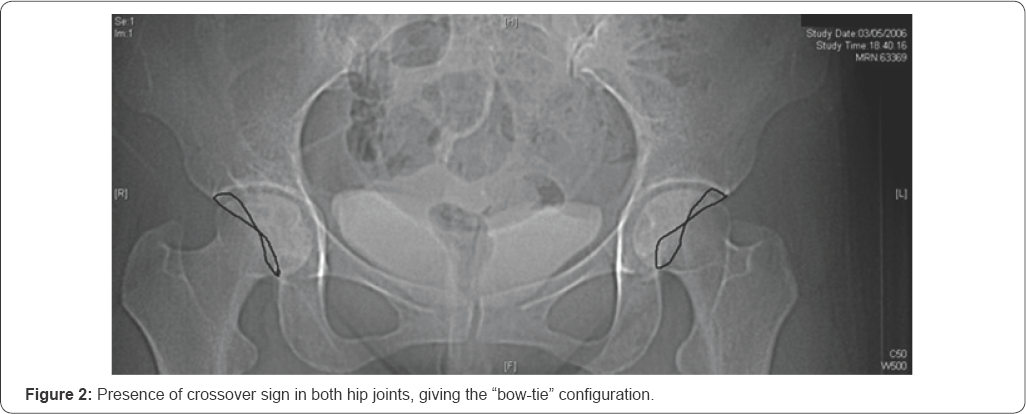

We obtained 44 relevant patients, 25 females and 19 males. On each one of the 88 hip joints we made the following measurements and observation: acetabular version angle, center edge angle, presence or absence of crossover sign. Version angle was evaluated on the orthogonal plane where the acetabulum cup is deeper, with two lines: the first one passing through the anterior and posterior rim of the acetabulum and the second one is perpendicular at the line passing through posterior acetabular rim bilaterally (Figure 1). The presence or absence of acetabular crossover sign was evaluated using the transparent 3-dimensional pelvis model, drawing the acetabular rim and checking if the anterior margin was crossing the posterior margin (Figure 2).